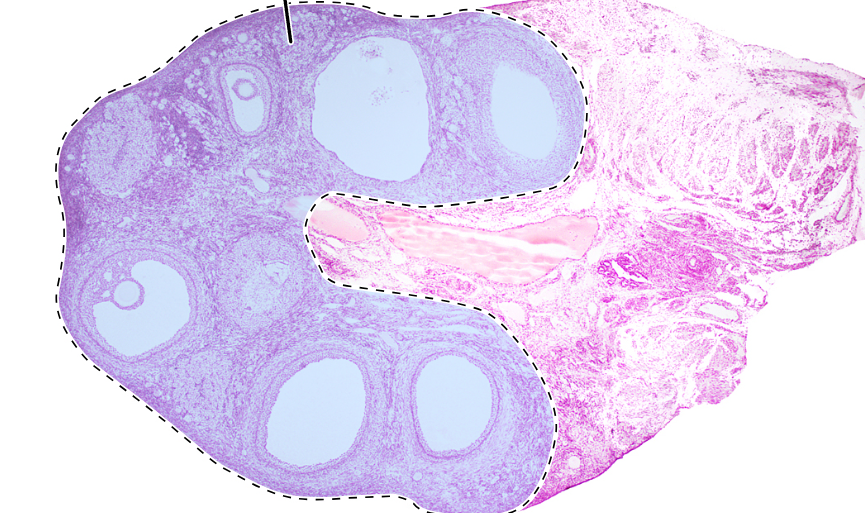

ovary (sagittal section)

primordial follicles

primary follicle

secondary follicle

antrum

tunica albuginea